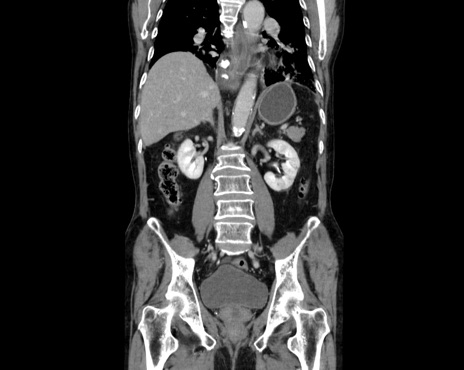

症例26(冠状断像)

【症例】80歳代男性

【主訴】嘔吐

【現病歴】昨晩2回嘔吐あり、今朝になっても嘔吐あり。来院。

【既往歴】胃潰瘍

【身体所見】意識清明、BT 37.6℃、BP 166/95mmHg、HR 100bpm、SpO2 97%、腹部:平坦・軟、腸蠕動音聴取良好、圧痛なし。

【データ】WBC 21900、CRP 1.4